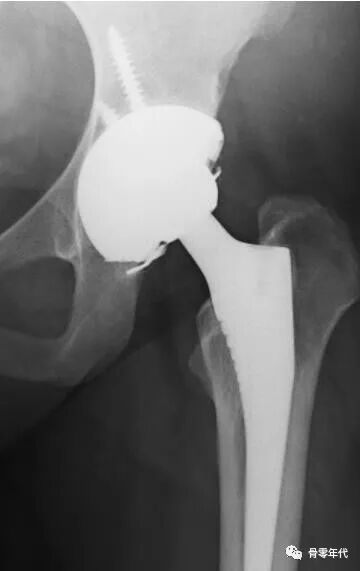

陶瓷内衬断裂的可能原因包括脱位、撞击、微分离、植入创伤和错位。为了减少陶瓷骨折,(Stryker,Mahwah,NJ)陶瓷髋臼衬里中增加了一个凸起的金属轮缘,以降低植入过程中陶瓷髋臼组件骨折或损坏的风险。

陶瓷髋臼衬里中增加了一个凸起的金属轮缘,以降低植入过程中陶瓷髋臼组件骨折或损坏的风险

陶瓷内衬背面金属环设计是为了减少陶瓷碎裂的风险,Kwong-Yin Chung认为这种设计的陶瓷杯错位安放率高,35例陶瓷对陶瓷全髋置换术患者资料,采用Trident髋臼系统,术后影像学检查发现,8例陶瓷杯错位安放,其中1例早期手术更换了陶瓷杯,其余7例平均随访14年,没有进行翻修术。运用细致的手术技术,在髋臼壳内实现适当的衬垫对齐,以最大限度地减少这种潜在的可纠正的错误。

x光片显示内衬安装不良,(箭头所指)之间存在间隙